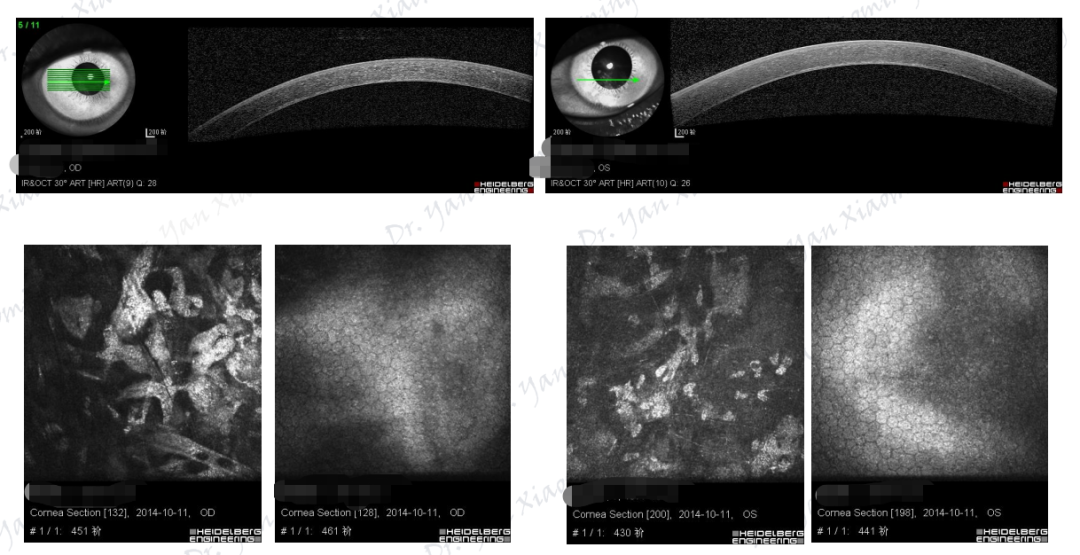

图片

图16.PPCD共焦镜检查:A-C.弯曲、带状高反光;C.囊泡状病变;D.蜗牛样病变;E、F.椭圆形、鳞状病变

图17.PPCD共焦镜检查:A、B.内皮细胞大小不一及多形性、巨大内皮细胞;C、D.有核内皮细胞;B、E.Guttata样暗点;F.内皮细胞层沉积物

(图片16、17来源:Cornea 2013;32:1237-42)